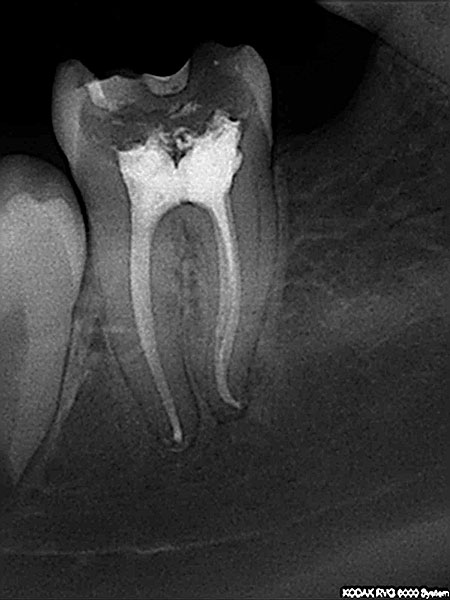

Endodoncija